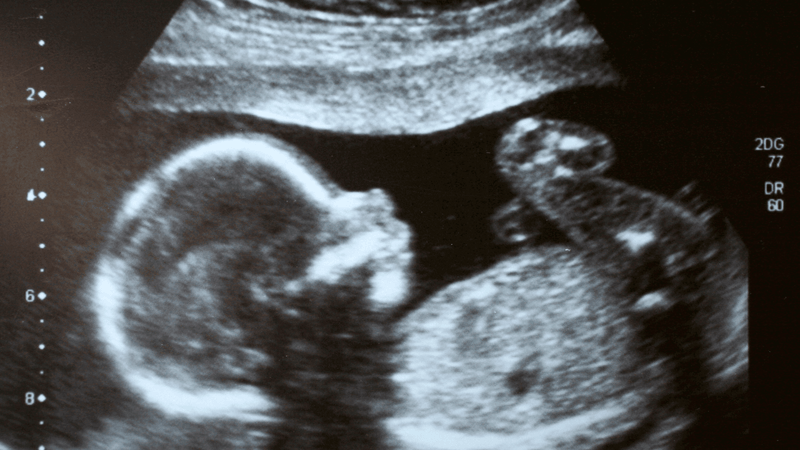

Siêu âm thai là một xét nghiệm được thực hiện trong thời kỳ mang thai, phương pháp này sử dụng sóng siêu âm để tạo ra hình ảnh của thai nhi trong tử cung người mẹ. Đây là công cụ quan trọng giúp bác sĩ theo dõi sự phát triển của bé, phát hiện các bất thường bẩm sinh và đánh giá tình trạng sức khỏe thai nhi.

Về mặt kỹ thuật, siêu âm thai có thể được thực hiện qua bụng mẹ (siêu âm bụng) hoặc qua đường âm đạo (siêu âm đầu dò), tùy thuộc vào giai đoạn thai kỳ và mục đích kiểm tra. Các bộ phận như tim, đầu, cột sống và tay chân của thai nhi đều được đánh giá kỹ lưỡng trong quá trình này. Với vai trò là “người bạn đồng hành” của mẹ bầu, siêu âm thai không chỉ mang lại thông tin y khoa mà còn giúp gia đình yên tâm hơn về sức khỏe của bé.

Đây là phương pháp truyền thống, sử dụng sóng siêu âm để tạo hình ảnh hai chiều cơ bản. Siêu âm 2D phù hợp để theo dõi kích thước, nhịp tim và sự phát triển chung của thai nhi, thường được dùng trong các mốc kiểm tra định kỳ.

Khác với 2D, siêu âm 3D cung cấp hình ảnh ba chiều chi tiết về khuôn mặt, tay chân và hình thái thai nhi, trong khi 4D bổ sung chuyển động thời gian thực - như cảnh bé ngáp hay mút tay. Những phương pháp này giúp phát hiện dị tật rõ ràng hơn và mang lại trải nghiệm đặc biệt cho cha mẹ.